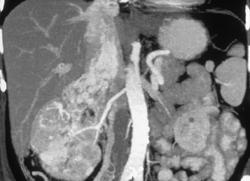

Retroaortic Left Renal Vein